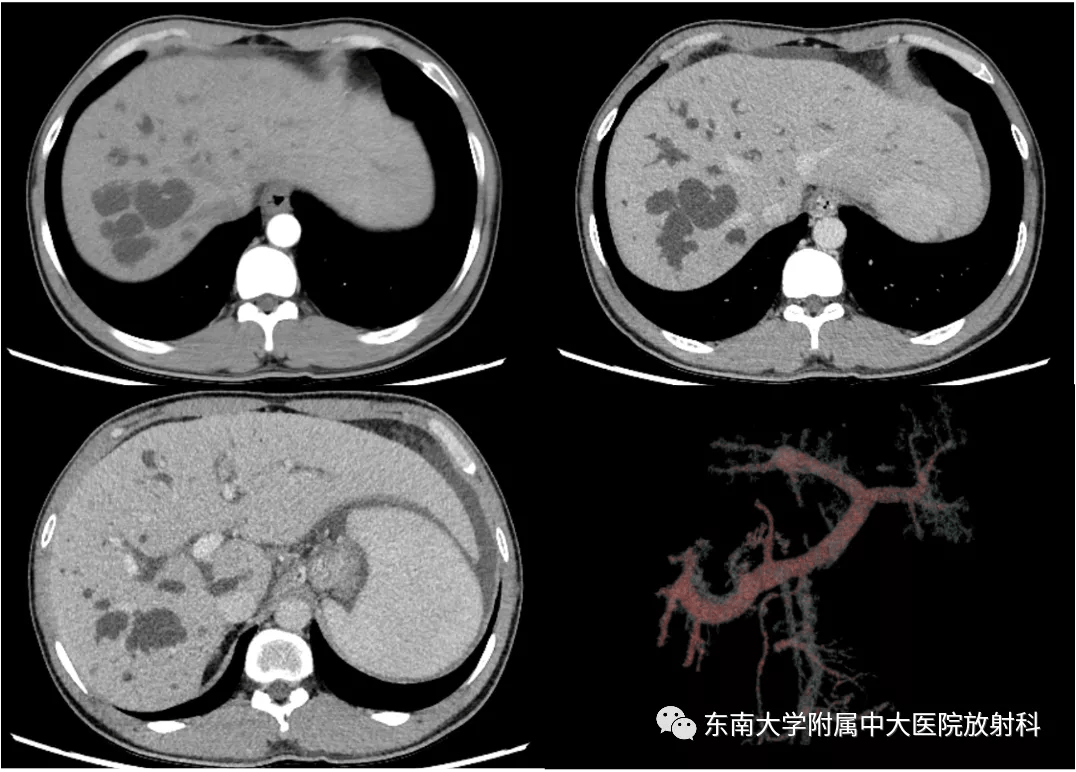

病例讨论与文献学习caroli病caroli综合征

图片尺寸960x540